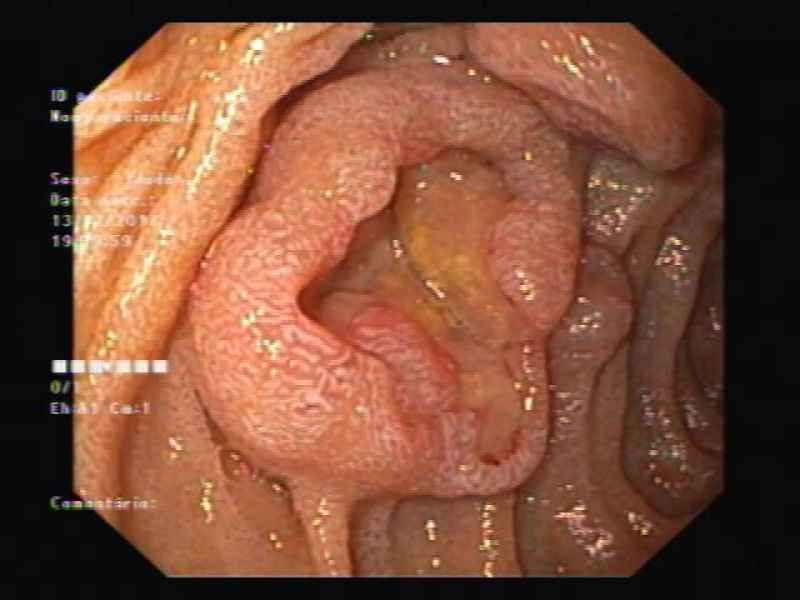

An unusual cause of upper gastrointestinal bleeding and small bowel obstruction

An unusual cause of upper gastrointestinal bleeding and small bowel obstruction

Maria Pia Costa Santos, Alexandre Ferreira, Vera Silveira, Luísa Glória, Marília Cravo

A 58-year-old black female, born in Angola, presented with melena, vomiting and a 7-year history of a right thigh mass that progressively increased in size. Her laboratory tests revealed iron deficiency anemia (hemoglobin 4.4g/dL). Computed tomography showed a large solid lesion in the right thigh, multiple smaller lesions in the lungs, pancreas and uterus, focal thickness of the small bowel wall and jejunal intussusception. Upper gastrointestinal endoscopy revealed multiple ulcerative lesions with elevated edges throughout the second and third portions of the duodenum, with 10-20 millimeters, without hemorrhagic stigmata. The histology of the duodenal and thigh lesions revealed a leiomyosarcoma.

An unusual cause of upper gastrointestinal bleeding and small bowel obstruction

Fotografia